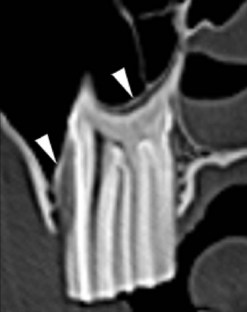

CT has proven to be very useful in the diagnosis of fractures, dental disease, infection and neoplasia of the equine head. Protocols for the use of CT in evaluating the equine head have been described in detail.28 Despite the fact that CT is increasingly used for the diagnosis of equine dental disease, comparatively little information has been published to date on the appearance of equine dental tissues in health and disease.

Technical principles

CT is a cross-sectional imaging method that uses a rotating X-ray tube and detector system located in a gantry for image acquisition. When the narrow X-ray beam passes through a selected plane of the body, it is partially absorbed when it passes through tissues with different attenuation coefficients (density). Each tissue is assigned a value that represents its attenuation coefficient. Computerized reconstruction programs are used to assign a gray scale value that correlates to the attenuation value of the tissue being imaged.32 Different algorithms can be used for image reconstructions.33 Each CT instrument manufacturer offers algorithms specifically designed for their individual hardware. For equine dental imaging, a soft tissue algorithm is useful for imaging of the soft tissue structures, followed by a reconstruction in a bone algorithm (high resolution) from the raw data, to allow detailed evaluation of dental and bony structures. The acquired sectional images can be reformatted in various two-dimensional planes or three-dimensional models (Fig. 13.51).

image image

Fig. 13.51 Three-dimensional reconstruction (A) of the bone surface image of an irregular depressed fracture involving the right frontal, nasal, lacrimal, and maxillary bones in a 5-year-old Friesian gelding. The location of fracture lines largely coincides with anatomical suture lines. The distribution and extent of these fractures are well highlighted in the 3D-reformation.